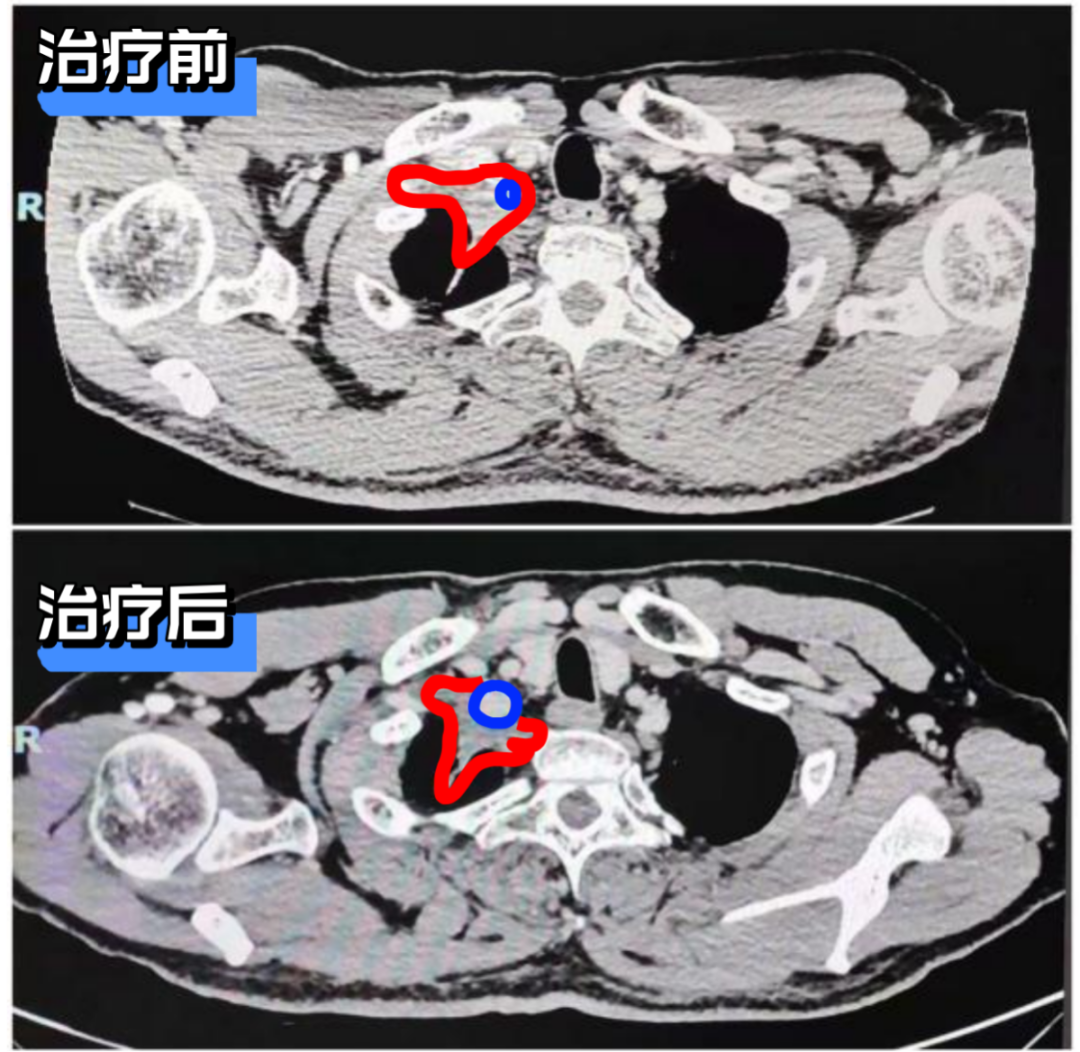

*右无名静脉情况:新辅助治疗前肿瘤侵犯包绕右无名静脉。治疗后肿瘤退缩明显,无名静脉显示清晰。